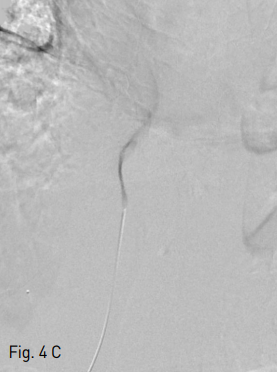

Fig 4C

Position of the needle into the left hepatic vein was confirmed by contrast injection (C).

Fig 4D

A 0.035-inch guidewire was passed through the left hepatic vein, IVC, right atrium and SVC into the right innominate vein. Then transhepatic wire was snared using snare catheter providing through-and-through access (D).